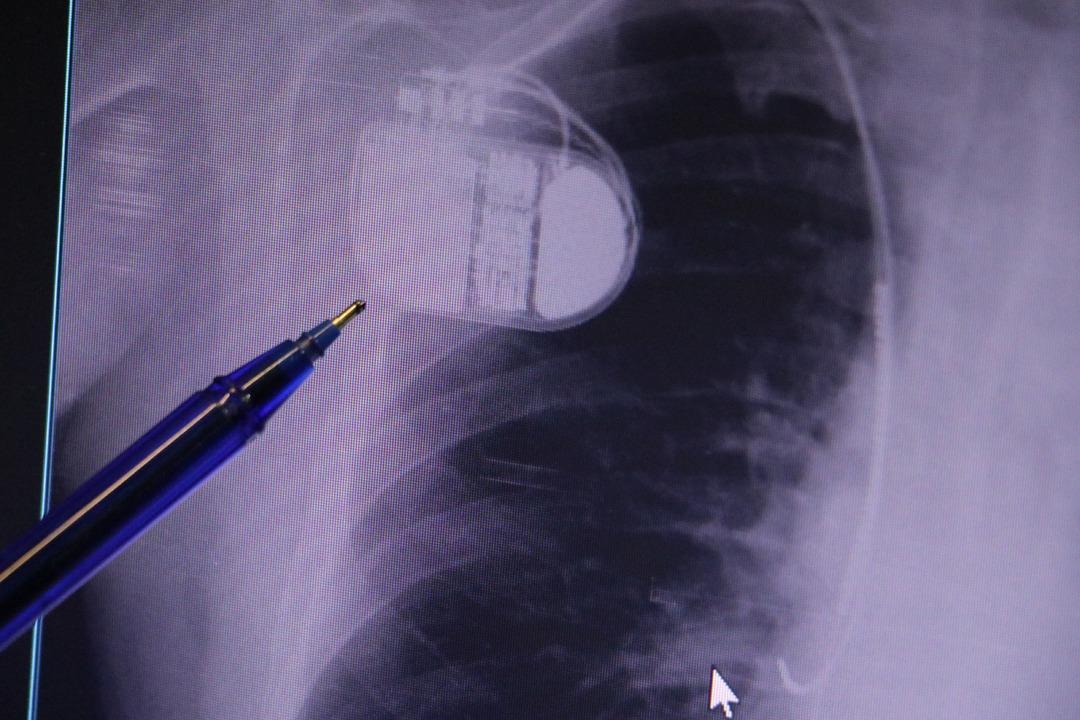

Konuya ilişkin açıklamalarda bulunan Kardiyoloji Bölümü Uzmanı Dr. İsmail Erdoğu, kalp pilinin önemine vurgu yaptı. Erdoğu, Yeni nesil kalp pillerinin MR cihazlarına girmeye imkan sağladığı, ancak tarama cihazlarından geçmenin önerilmediğini ifade ederek, "Soğuk hava nedeniyle oluşan titremeler, kalp pilinin kalbin durduğunu sanmasına ve yanlış şoklamaya yol açabilir. Bu nedenle hastalarımızın bu dönemlerde daha dikkatli olmalarını öneriyoruz" dedi.

Kalp pilleri ile MR cihazına girilebileceğini belirten Erdoğu, "Çok büyük bir ameliyat değil ama yine de ciddi bir cerrahi işlem. Kalp pili, tıpta son 30 yılda yaşanan gelişmelerden en büyüğü. Bir bilgisayarın küçültülüp insan vücuduna konulmuş hali aslında. İnsan ömrünü ciddi oranda uzatan bir tedavi. İnsanlar bir şokla hayata tutunurken, pil olmasaydı öleceğini düşündüğümüz birçok hastamız var. Kalp pilinin bu özelliği, uygun hastalarda ciddi oranda ani ölümü engelliyor. Hastanın başına gelecek bir kalp durması durumunda yanında bir sağlıkçı yoksa, onun ritmini düzeltecek defibrilatör cihazı yoksa hastayı hayatta tutmak mümkün değil. Uygun endikasyonlarda kalp pili olduğu zaman, pil hastaların ritmini algılıyor ve acilde yapılan şoklamayı yaparak hastayı hayata döndürüyor. Kalp pillerinde yeni teknolojilerle MR'a girmek mümkün, tomografiye zaten girebiliyorlar. Tarama cihazlarından geçmelerini uygun görmüyoruz. Bu tarz durumlarda hastalarımız 'kalp pilim var' dediğinde muaf tutuluyorlar. Kalp pilleri ciddi teknolojik cihazlardır. Vücudun içindeki titreşimi, örneğin mikser kullanmak, kolunu sallayacak herhangi bir eylem kalp pilinde olumsuz etki oluşturabilir. Soğuk havalarda vücutta oluşan ciddi titremeler kalp pilinin hafızasını karıştırıp kalbin durduğunu düşündürebilir ve gereksiz şoklama yapabilir. Bu tarz kişilerin soğuk havalarda daha temkinli olması gerekir" dedi.